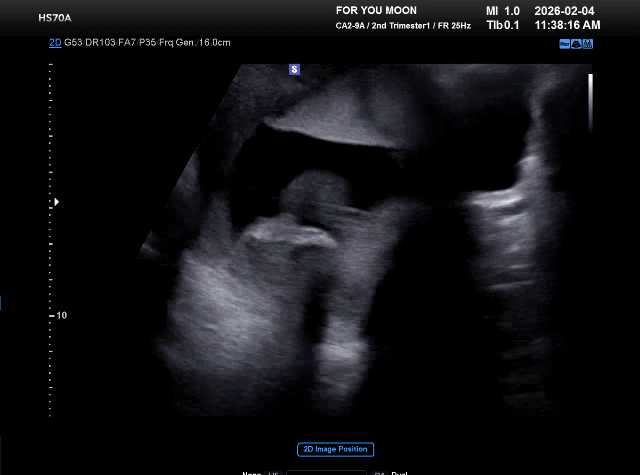

성별

이제 19주차인데 16주에 애가 안움직여서 원장님이 배도 흔들어보고 기침도 해봤는데 꼼짝도 안해서 아직 성별을 몰라요ㅠㅠ 내일 초음파 검사하는데 내일은 성별 알수 있겠죠?? 성별 아는 팁이 있을까요? 그리고 부모님께 성별 알릴때 어떤 이벤트??를 해드리면 좋을지 추천 부탁드립니다